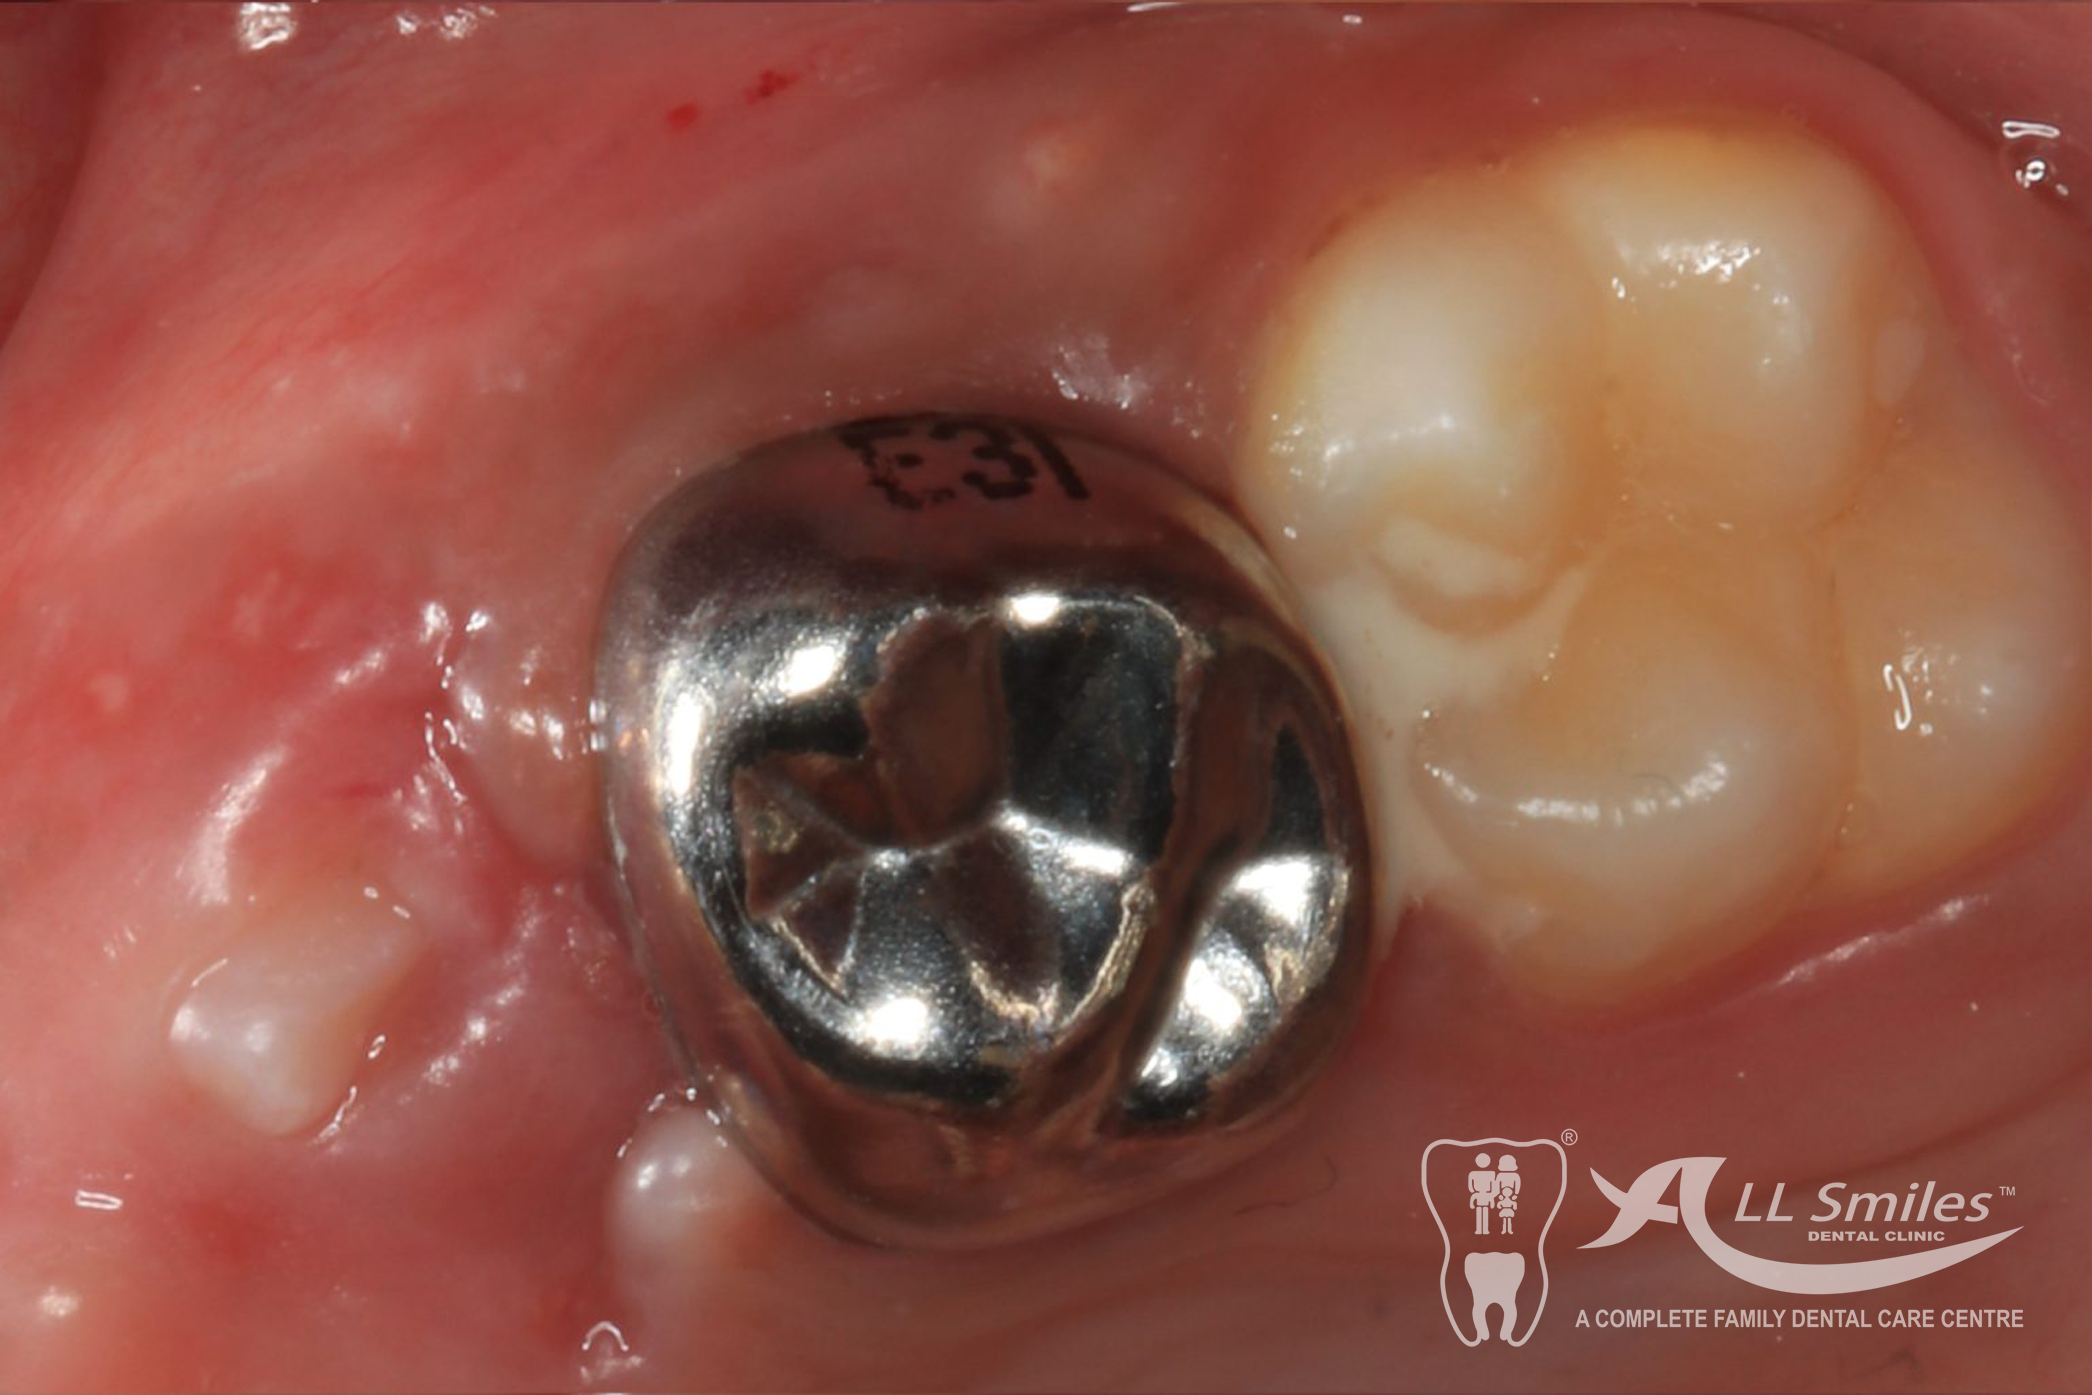

Crowns are tooth-shaped caps that cover and protect damaged or weakened teeth. They are commonly used for baby teeth that have extensive decay or are at risk of fracture.